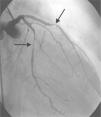

A 64-year-old white woman with a history of hypertension was admitted to hospital with new-onset chest pain consistent with angina. She had had multiple coronary angiograms (CA) four years previously for repeated episodes of typical chest pain and admissions. The CA showed non-obstructive coronary artery disease in the range of 40–50% in the left circumflex artery (LCx) which was confirmed to be non-obstructive by fractional flow reserve during the angiogram; no catheter-induced vasospasm occurred during the CA. Because of continued episodes of chest pain, she was taken off metoprolol and started on diltiazem 240mg once a day for possible vasospastic angina. She was then asymptomatic for the following four years, and also had a dobutamine stress echocardiogram, which was negative, about two months before the present admission for screening due to disease identified on her last CA. At this admission, she had new symmetrical anterolateral and inferior T inversion on the ECG consistent with ischemia; troponin levels were minimally elevated (0.3ng/ml). The patient had been seen by her primary care physician three days previously for a routine follow-up and was taken off diltiazem and started on nebivolol 10mg/day in addition to her medications of HCTZ 25mg and lisinopril 40mg/day, Lipitor 40mg, and enteric-coated aspirin 325mg/day for blood pressure (BP) control. In hospital she was started on nitro paste and intravenous (IV) heparin and her home medications continued. Because of continued chest pain in hospital and mildly elevated troponin I levels, she was scheduled for CA. She experienced chest pain at the beginning of the coronary angiogram, which initially revealed a 70% lesion and slow flow in the mid left anterior descending artery (LAD), a 90% lesion in the mid LCx and a 99% lesion in the ostium of the second obtuse marginal (OM2) (Figure 1, black arrow). The right coronary artery (RCA) had a distal 80–90% stenosis (Figure 2, black arrow). During preparation for percutaneous intervention in the LCx and OM2, intracoronary (IC) nitroglycerin was given for vessel sizing, after which there was resolution of the lesions in the LAD and decrease in the mid left LCx lesion to 50–60%, and resolution of the OM2 lesion, suggestive of significant reversible coronary artery spasm (Figures 3 and 4, white arrows). IC nitroglycerin was also administered in the RCA, in which lesion resolution was also seen. The coronary intervention was aborted, the patient's chest pain was resolved after IC nitroglycerin and she was started on IV nitroglycerin in the interim. Nebivolol was discontinued; diltiazem started in post-catheterization orders. She continued to have occasional episodes of chest pain for about 24hours after discontinuation of nebivolol. She was weaned from IV nitroglycerin the next day and started on oral isosorbide mononitrate. The following day the ECG changes resolved with no more episodes of chest pain; she was discharged home and was event-free in follow-up.